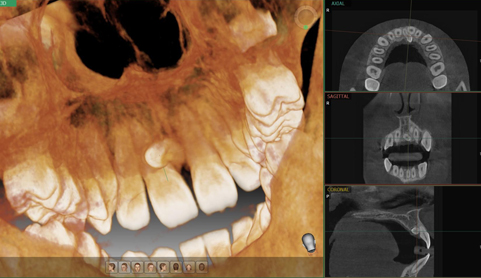

네비게이션 임플란트

디지털 시뮬레이션을 통한 정확한 식립 위치와 깊이 진단.

임플란트 식립위치 선정

치아가 빠진 자리에 정교한 임플란트 식립.

임플란트 공간 확보를 위한 정확한 진단.